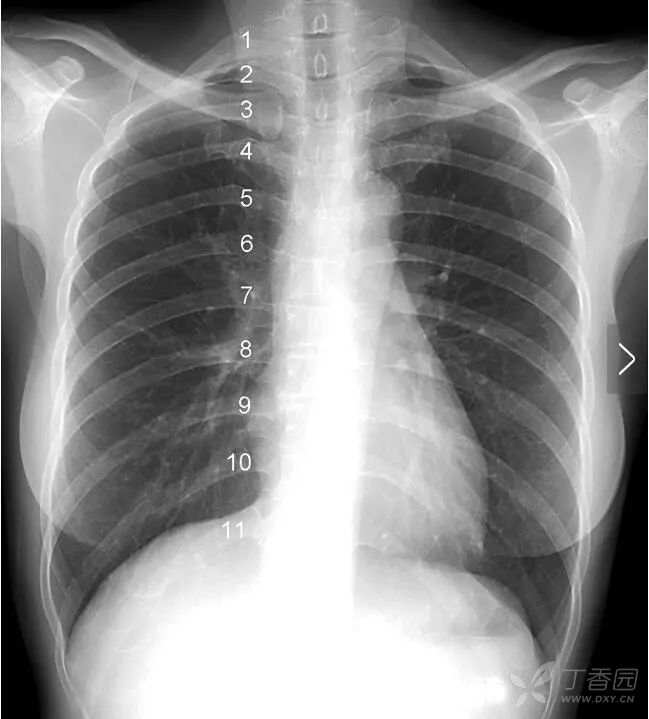

肋 骨 一根肋骨在正位胸片上投影的前后端并不在同一水平,为了便于描述,肋骨被人为的分为后段(后肋)和前段(前肋)两个部分。后段通常是肋骨从胸椎到肺野外缘的投影,走行大致水平或略向外下倾斜。前段从肺野边缘起向内下呈比较大角度的斜向走行,越是接近第11、12肋的肋骨,其前段向下倾斜的角度越大。

图中1~11分别标示第一到第十一后肋。

图中1~10分别标示第一到第十前肋。